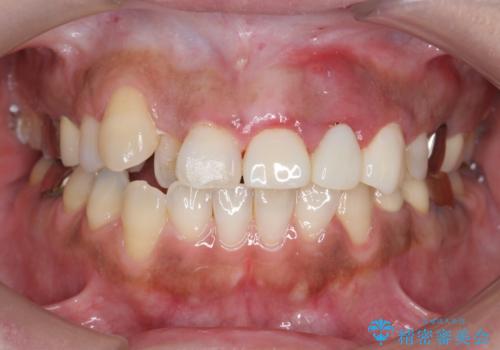

今回用いたオールセラミッククラウンは、ジルコニアフレームという白い素材の上にセラミックを盛っているため審美性が非常に高いのが特徴です。

またジルコニアは人工ダイヤモンドの材料にも使われているほど高い強度を持っており、そのためオールセラミッククラウンは審美性だけでなく、奥歯やブリッジの補綴も可能とするクラウンです。